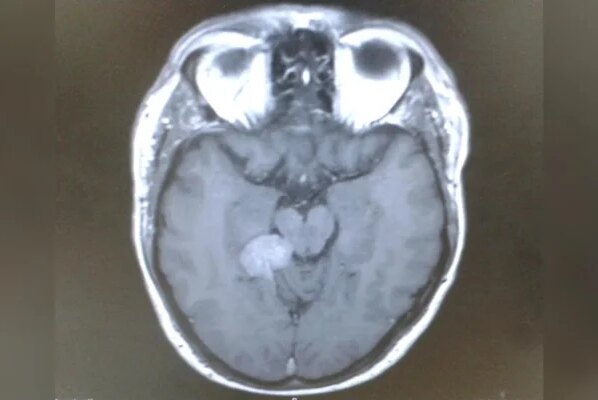

A confirmação veio em março de 2015. Após ser encaminhado a um neurocirurgião, Darren recebeu o diagnóstico de um meningioma tentorial em estágio inicial.

Trata-se de um tumor geralmente benigno e de crescimento lento, que se desenvolve a partir das meninges, as membranas que envolvem o cérebro. No caso dele, a lesão estava localizada na base do cérebro, em uma área considerada inoperável por causa dos riscos do procedimento.

Apesar de não ser canceroso, esse tipo de lesão pode causar uma série de sintomas ao pressionar estruturas cerebrais e nervos. Entre eles estão zumbido no ouvido, dores de cabeça, alterações na visão, perda auditiva, diminuição do olfato e dificuldade para engolir. Se não tratado, pode se tornar potencialmente fatal.

A confirmação veio em março de 2015, quando ele foi encaminhado a um neurocirurgião